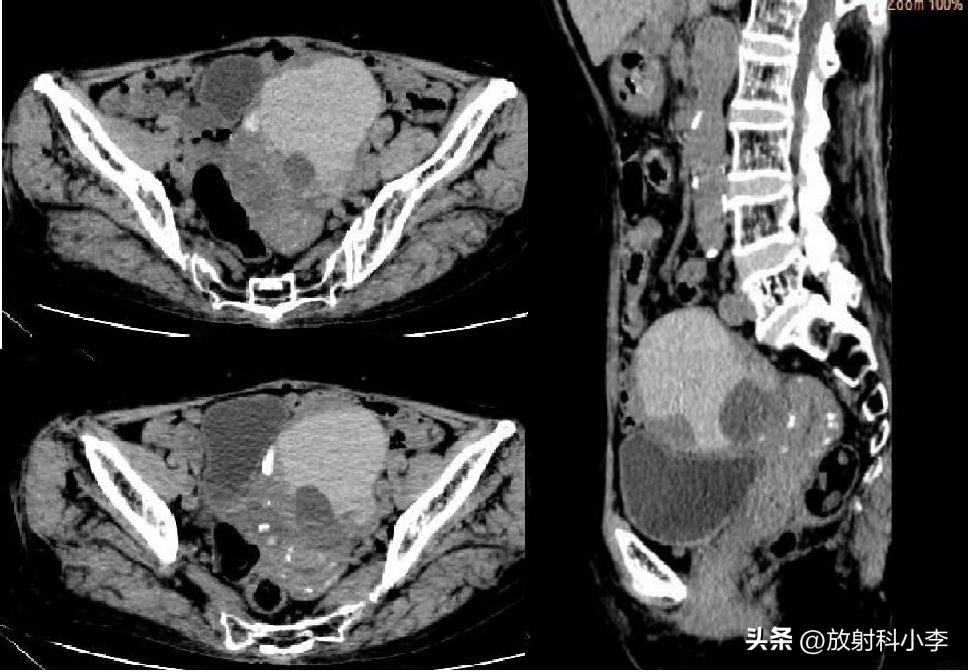

F,27Y

增强CT示子宫前无强化实性肿块,而双侧卵巢正常;失状位示子宫前壁附着蒂扭曲。